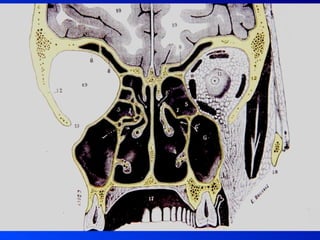

SINUSITIS Interrogatorio SintomatologíaExamen Físico Palpación – percusión Rinoscopia anterior Rinoscopia posterior Exámenes complementarios Imagenología: Rx, TAC, RM Fibroscopía - Endoscopía Punción DIAGNOSTICO

• 29.

• 30.

• 31.